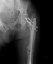

Насчет ревизионного штифтования - вот пример, вчера сделали.

|